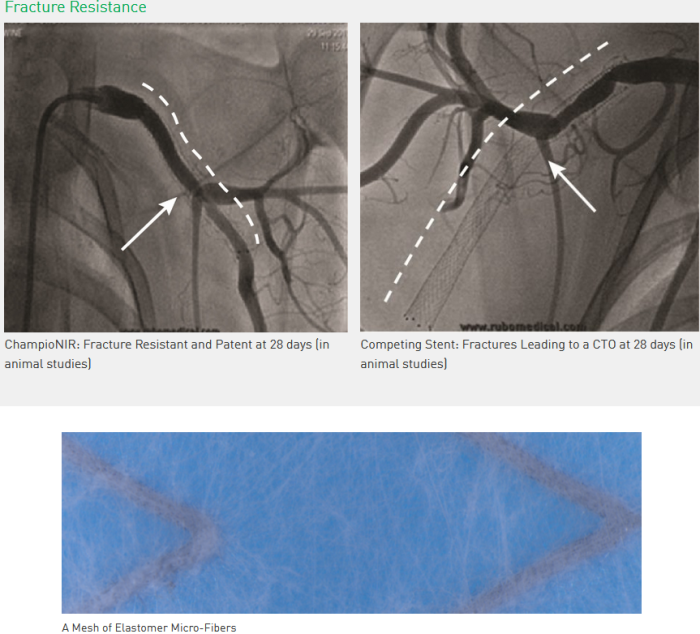

ChampioNIR is a hybrid stent combining Nitinol alloy structure with an elastomer micro-fiber mesh. Fracture resistance during contraction, compression, torsion, extension and flexion. Outstanding radial support and conformability to the vessel natural form and motion. Unique delivery system for accurate stent deployment. Superior flexibility for better deliverability. ChampioNIR is the first peripheral stent to offer a viable option for long-term stenting of peripheral arteries.

- The superficial femoral (SFA) and popliteal arteries are subject to extreme mechanical forces and constant extension, contraction, torsion, compression, and bending

- Traditional peripheral stenting has long been hindered by short effective stent life due to fracturing, leading to restenosis and occlusion